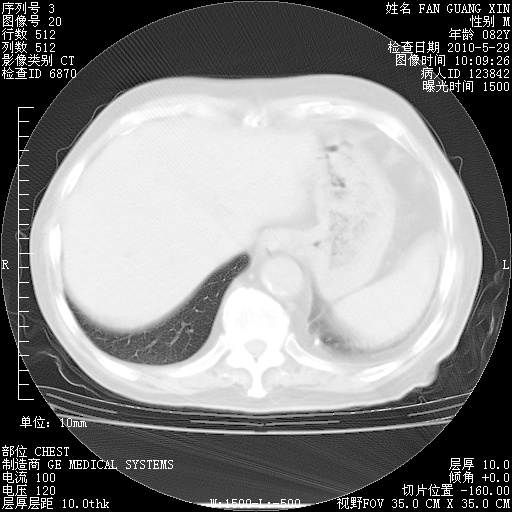

治疗3周后的肺部CT纵隔窗

再治疗10天后的肺部CT

再治疗10天后的肺部CT 纵膈窗

阅读此次胸部CT,肺间质渗出性改变较入院时有吸收。目前从体温、白细胞、中性分叶明显增高,肯定存在细菌感染(发生医院感染哦,若无消化道及泌尿系统等感染的依据,肺部感染可能大)。若你院头孢哌酮舒巴坦钠耐药率较高,同意你的方案,若48小时体温仍高,可考虑使用碳青霉稀类抗菌药物,同时可予超声雾化、注意滴数时加大液体量。白蛋白33.30g/L较低哦,需加强营养等支持治疗。